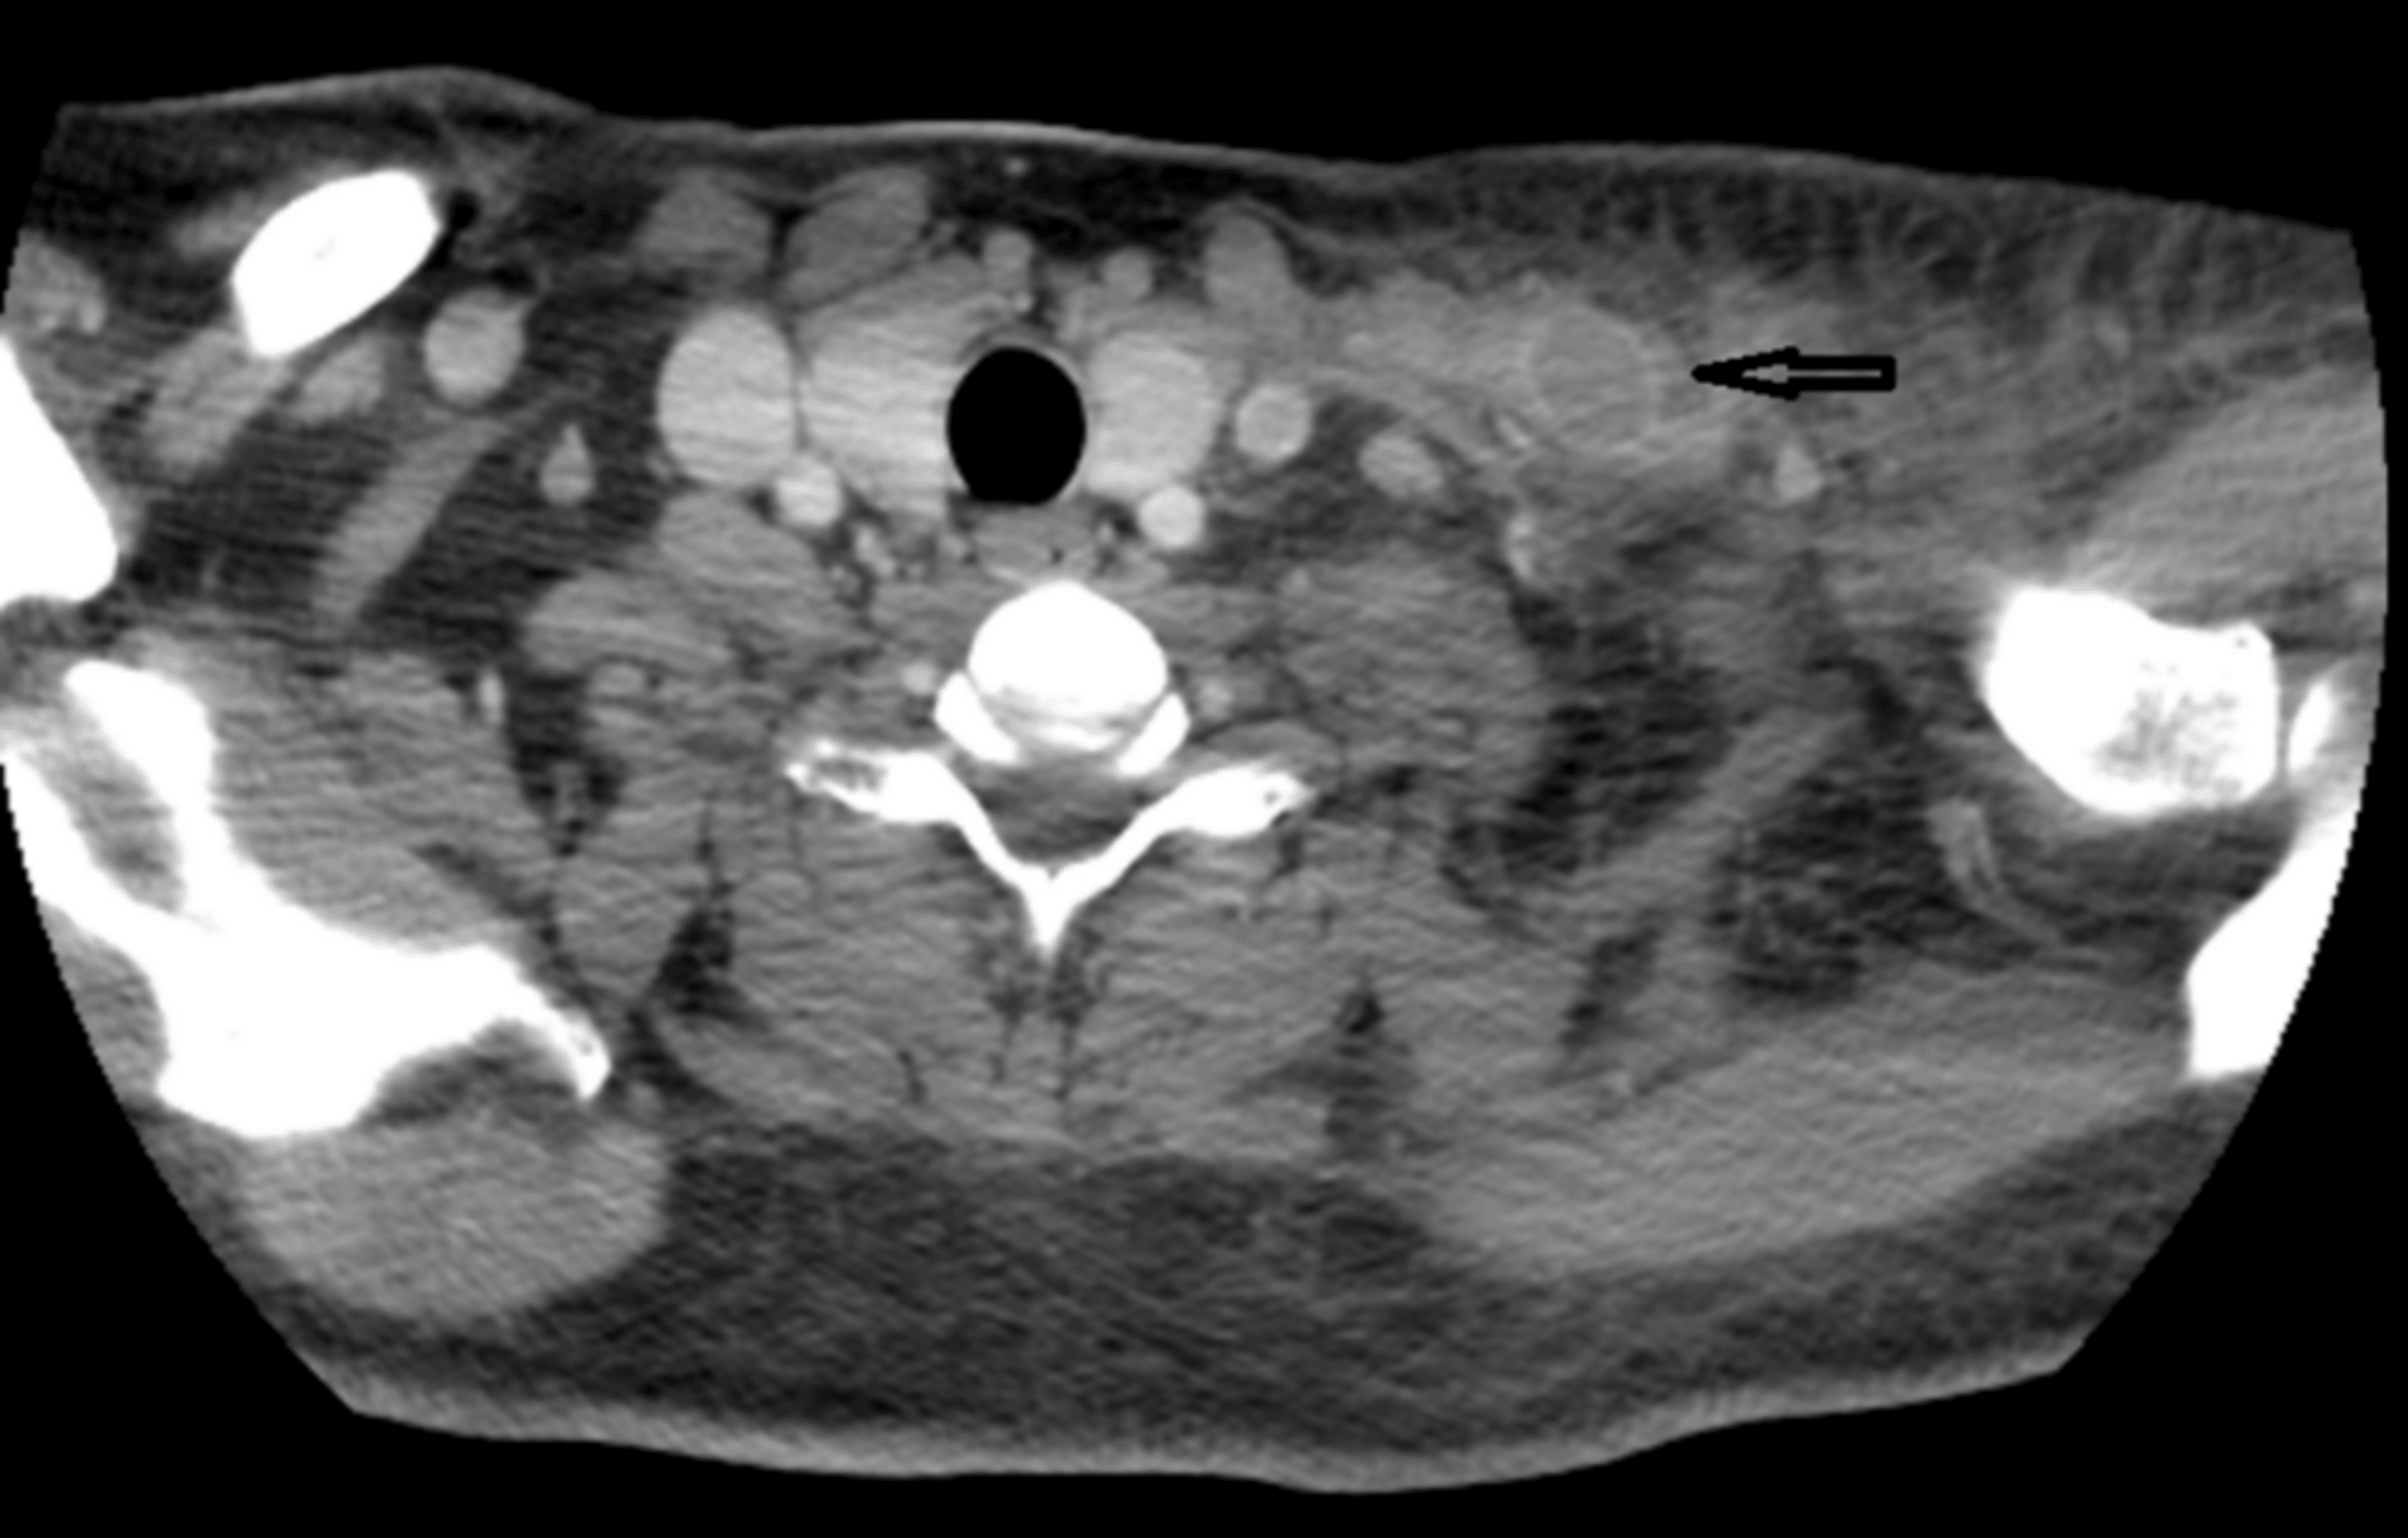

External jugular vein pseudoaneurysm Image Problems With External Jugular Vein Doctors call the pressure in the vena cava, which is a large vein, jugular venous. Jugular vein distention can signify heart failure and other cardiovascular problems. If you ever see someone with a bulging neck vein, you’re looking at the external jugular vein. Gross distension of the external jugular veins is often more easily observed than distension of the deeper. Problems With External Jugular Vein.